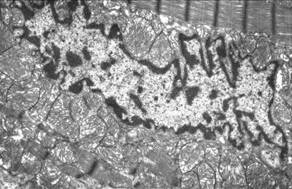

Апоптотическое тело, окружённое фрагментированной мембраной (E.Arbustini и соавторы, 2008)

●       Фагоцитоз макрофагами апоптотических тел

Поглощение макрофагом апоптотических тел (E.Arbustini и соавторы, 2008)

●       Фрагментация ядра и цитоплазмы с образованием мелких, окружённых мембраной апоптотических тел;